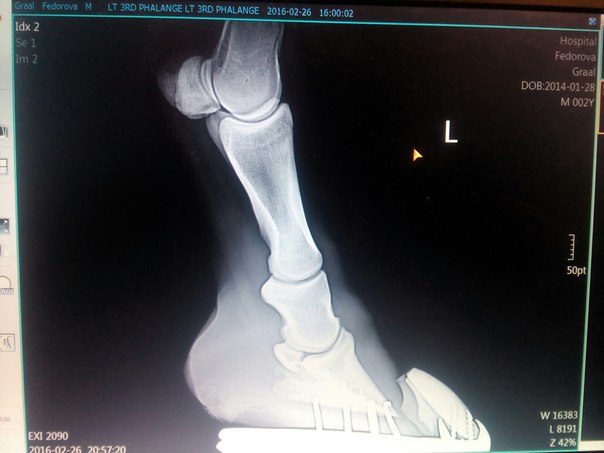

и буквально 2 нед.назад заметила что с передними ногами начинается беда, особенно с левой передней, начинается контрактура , бабка выходит вперед, созвонилась с ветеринаром, по ее рекомендациям ватники бинты в денник и гулять, до ее приезда, снять с овса. Пока ее ждали почти неделю, ноги стали хуже на левой ноге пятка выше стала . Вчера она до нас доехала , сказала, что есть шанс что то исправить , и такая проблема у него из-за его роста ,связки и сухожилия не успевают за ростом костей.